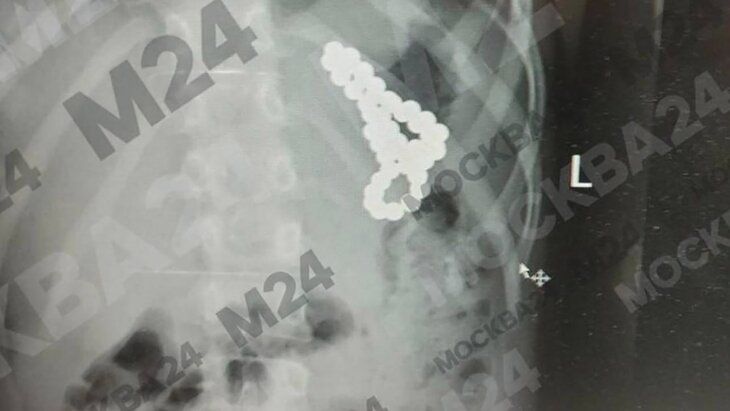

Московские хирурги спасли школьницу, проглотившую 46 магнитных шариков